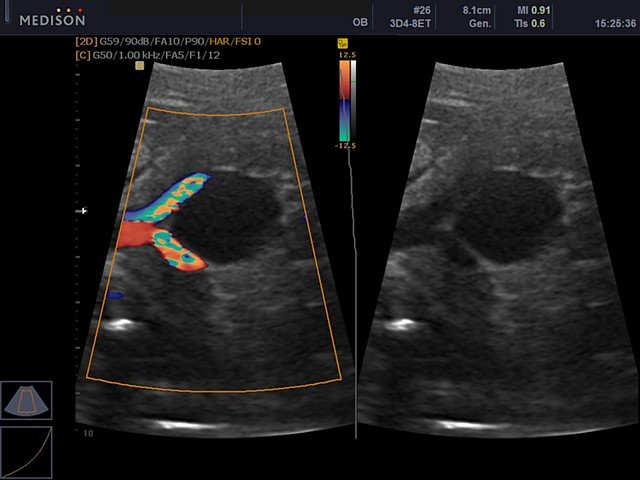

Артерия пуповина, энергетический допплер

Артерия пуповины, направленный энергетический допплер